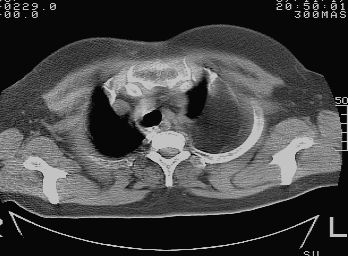

标题: CT10753:女, 64岁 隔疝 [打印本页]

标题: CT10753:女, 64岁 隔疝

女, 64岁 三十年前胸部外伤史, 间断胸闷,

典型左侧膈疝,疝出物为胃和大网膜,纵隔右移

同意左侧膈疝,不过,有过外伤史,左肺有受压征象,同时有胸膜增厚。

左侧隔疝(创伤性?),与外伤关系大。